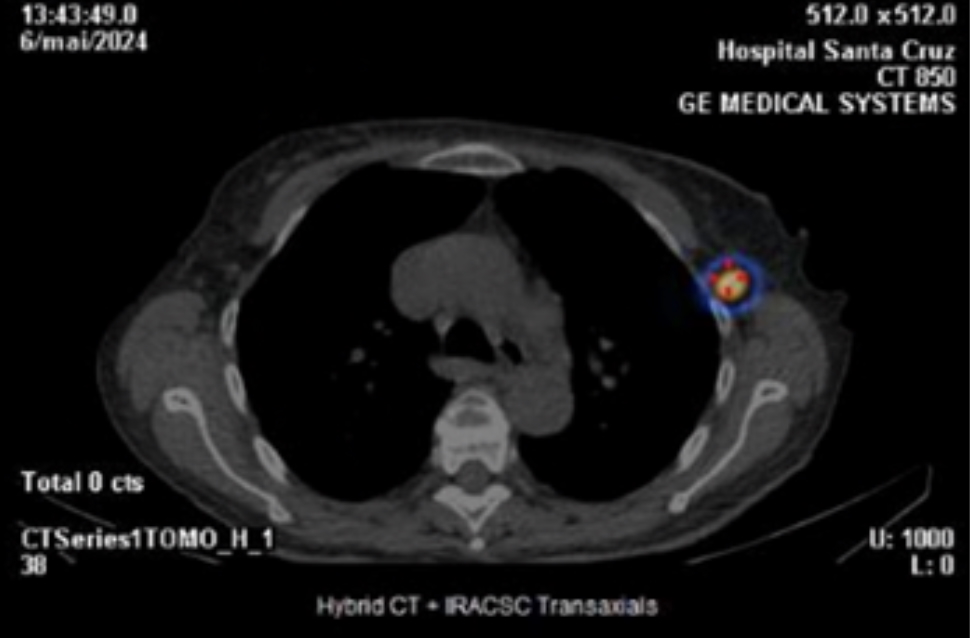

Preoperative lymphoscintigraphy scan revealed a drainage route to the sentinel lymph node in the contralateral axilla (Fig 1 and 2). In May 2024, she went under right simple mastectomy, right axillary lymph node dissection (“no show” of sentinel lymph node), and left sentinel node biopsy.

Fig. 2 - SPECT/CT images show a high intensity deposit in the left axilla, which was considered the sentinel node of the right breast cancer - axial cut.